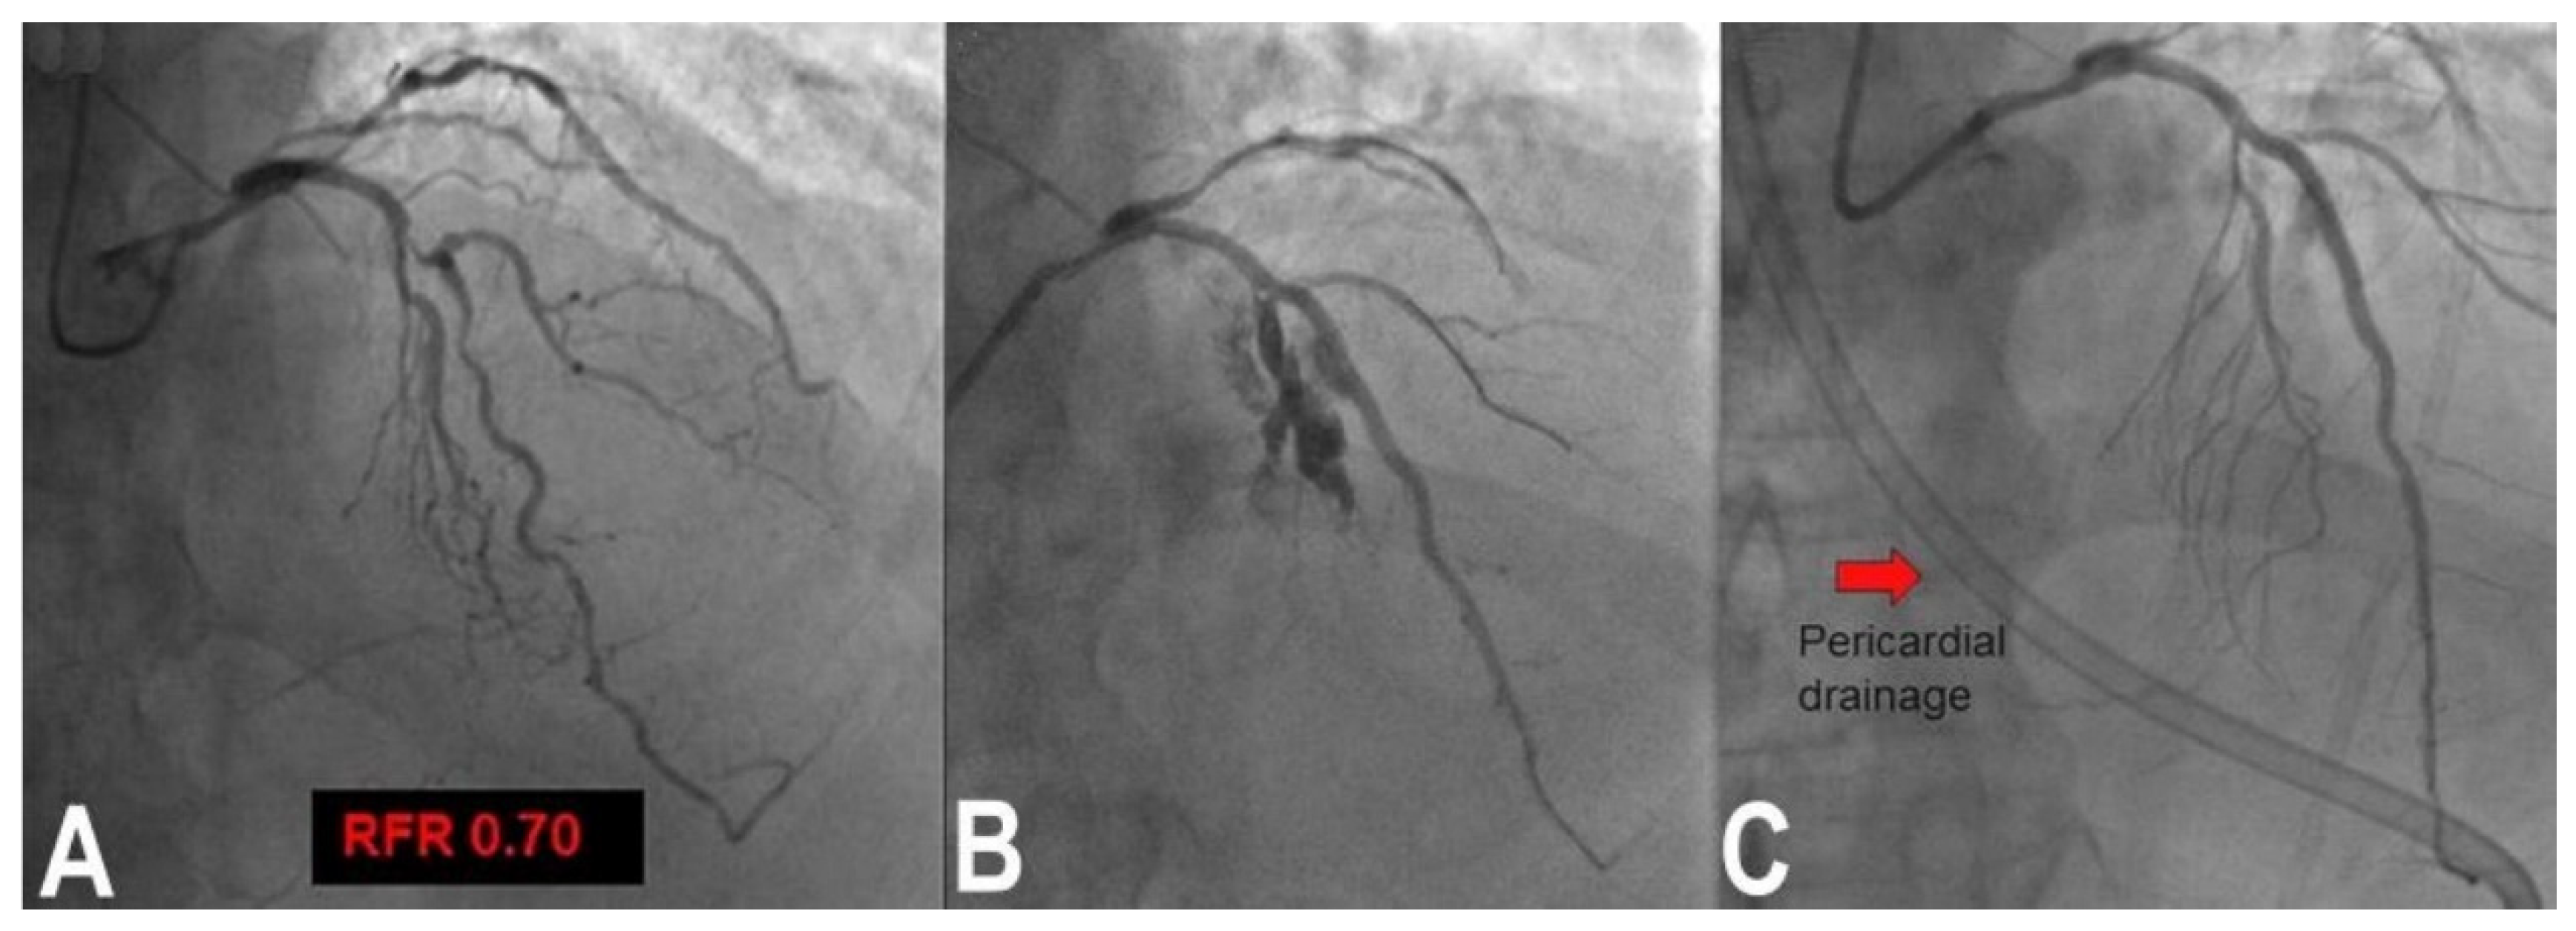

3.6. Perforation/Vessel Rupture

3.7. Wire Entrapment and Fracture

- Rigatelli, G.; Zuin, M.; Roncon, L. Unexpected huge post-stenting coronary perforation during complex left main revascularization. Turk Kardiyol. Dern. Ars. 2022, 50, 66–69. [Google Scholar] [CrossRef] [PubMed]